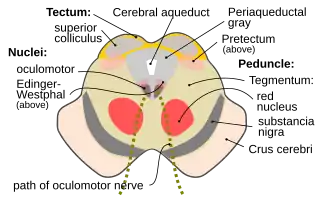

Section through superior colliculus showing path of oculomotor nerve. Periaqueductal gray is the gray area just peripheral to the cerebral aqueduct. | |

The periaqueductal gray is the gray matter located around the cerebral aqueduct within the tegmentum of the midbrain. It projects to the nucleus raphe magnus, and also contains descending autonomic tracts. The ascending pain and temperature fibers of the spinothalamic tract send information to the PAG via the spinomesencephalic pathway (so-named because the fibers originate in the spine and terminate in the PAG, in the mesencephalon or midbrain).